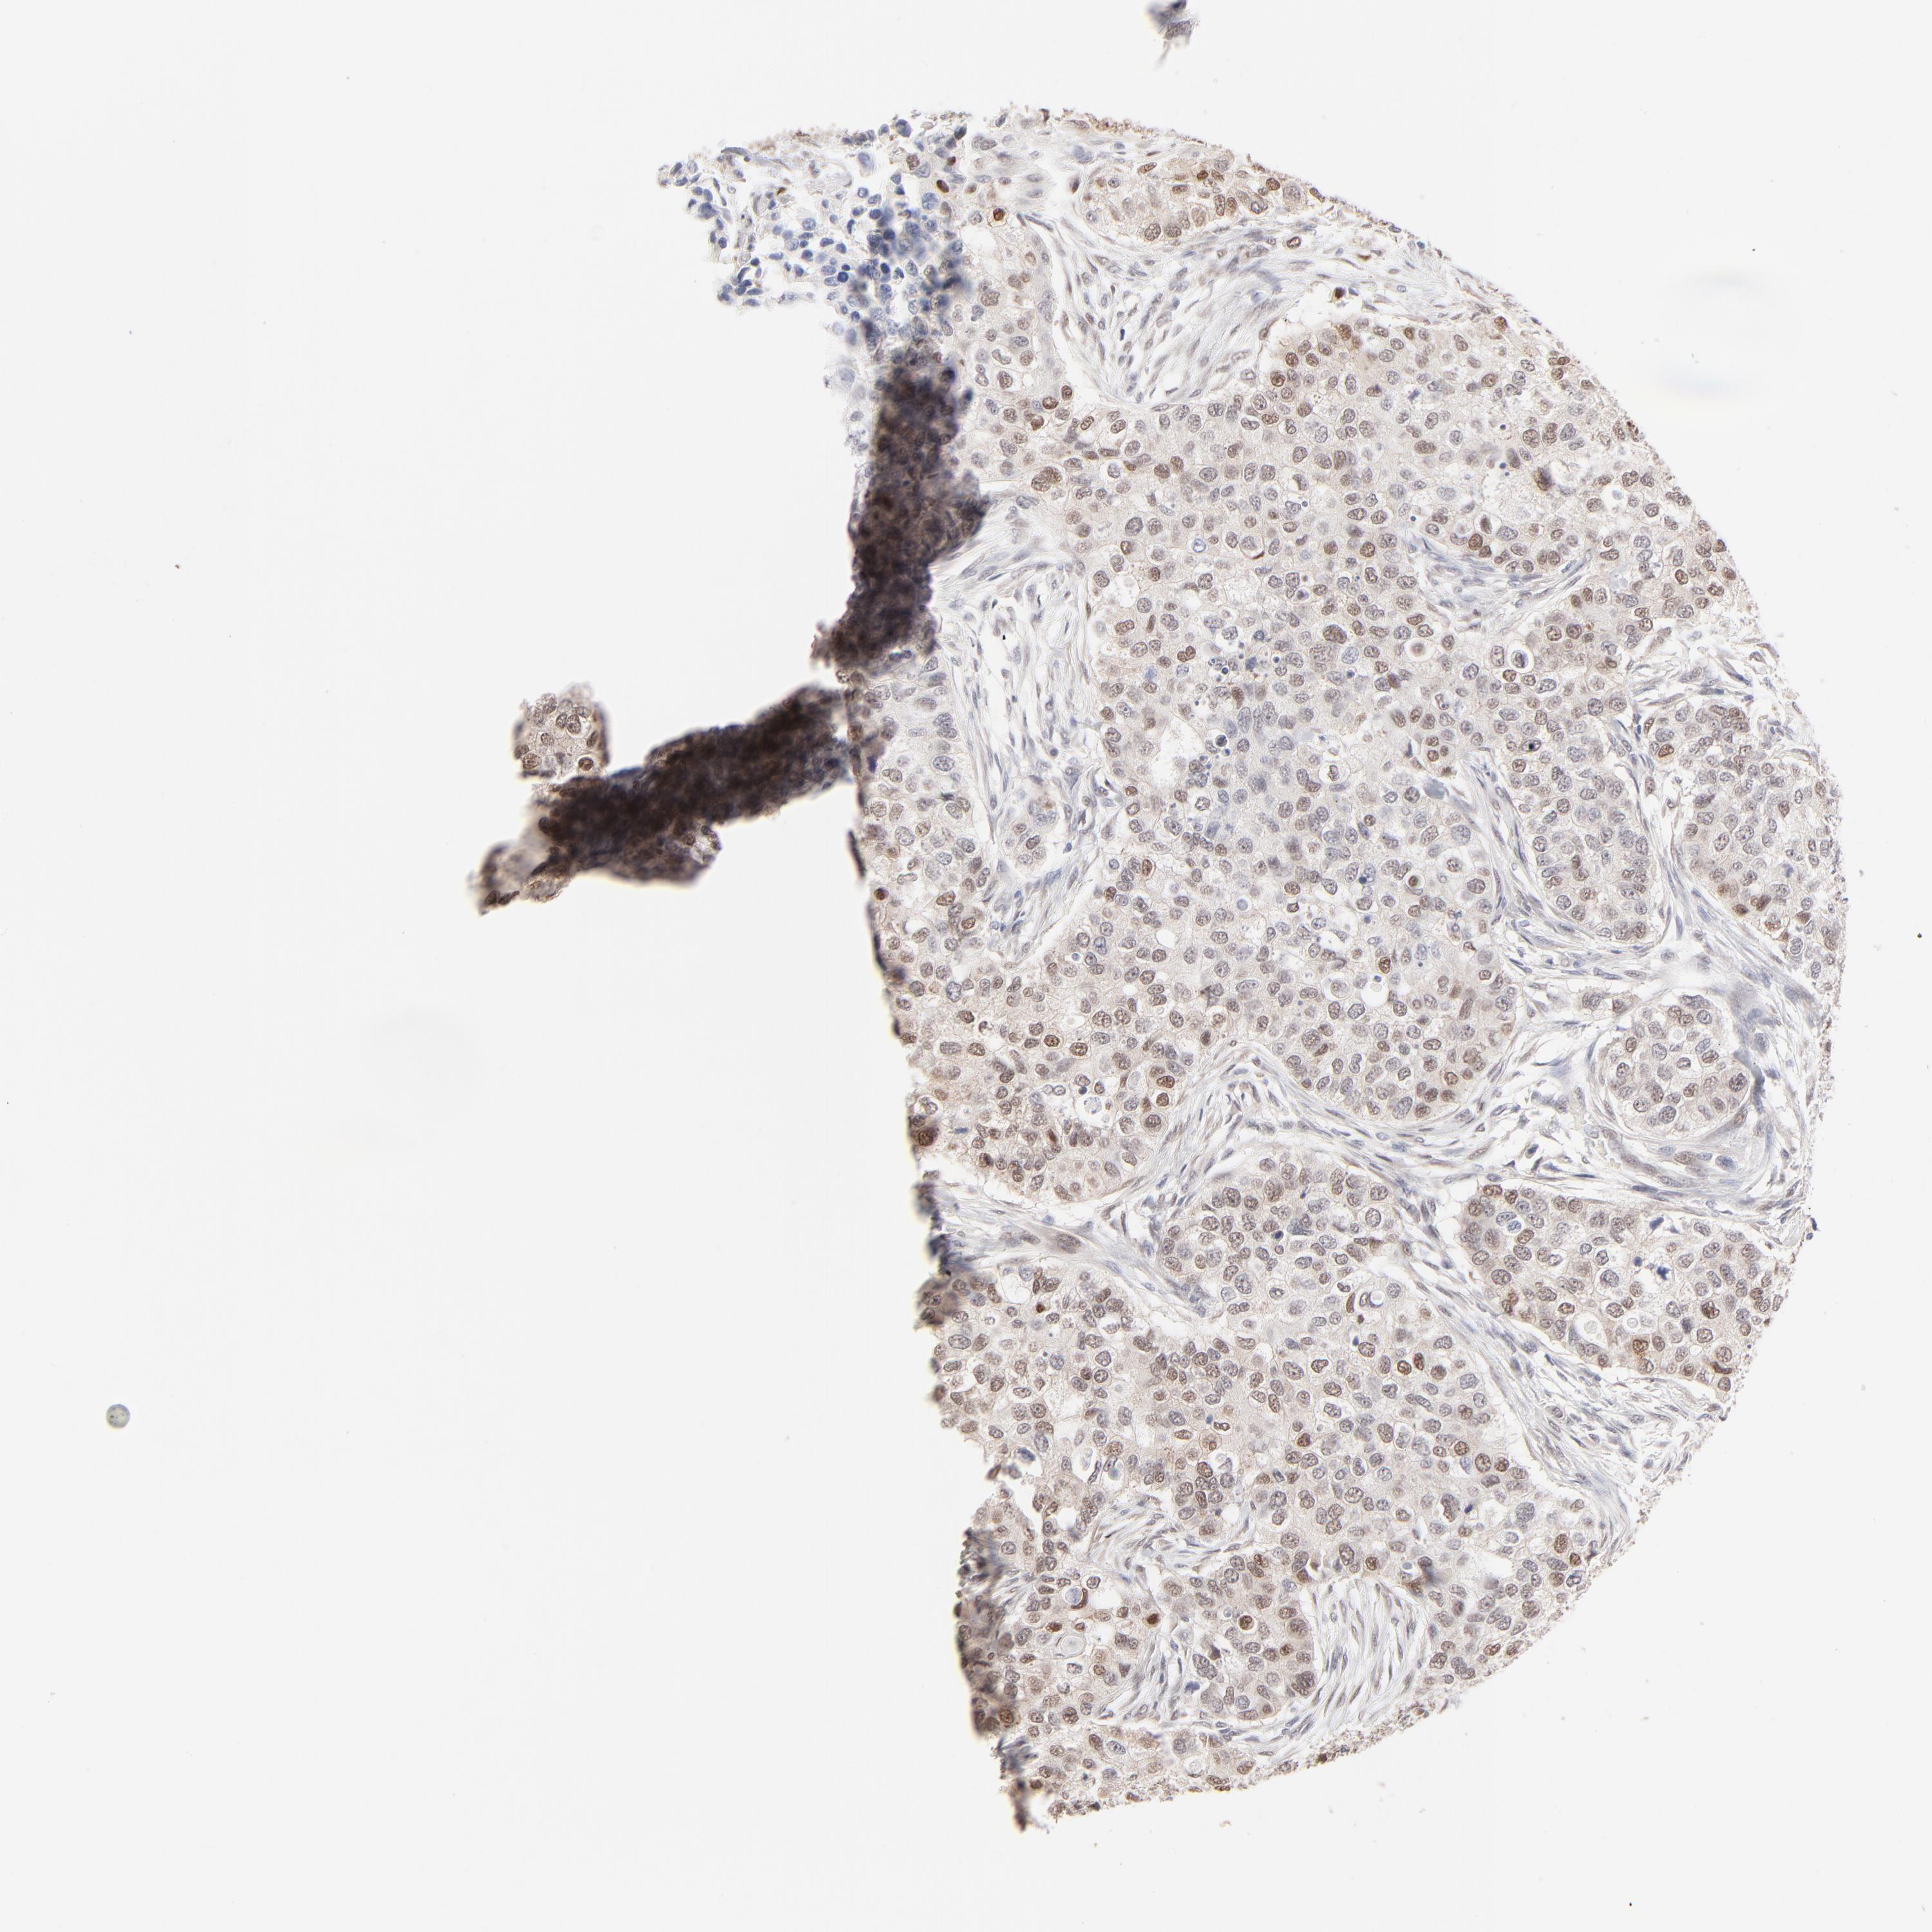

CANCER BREAST CANCER Show tissue menu

BRCA TCGA BRCA VALIDATION PROTEIN EXPRESSION

ANTIBODIES

AND

VALIDATION